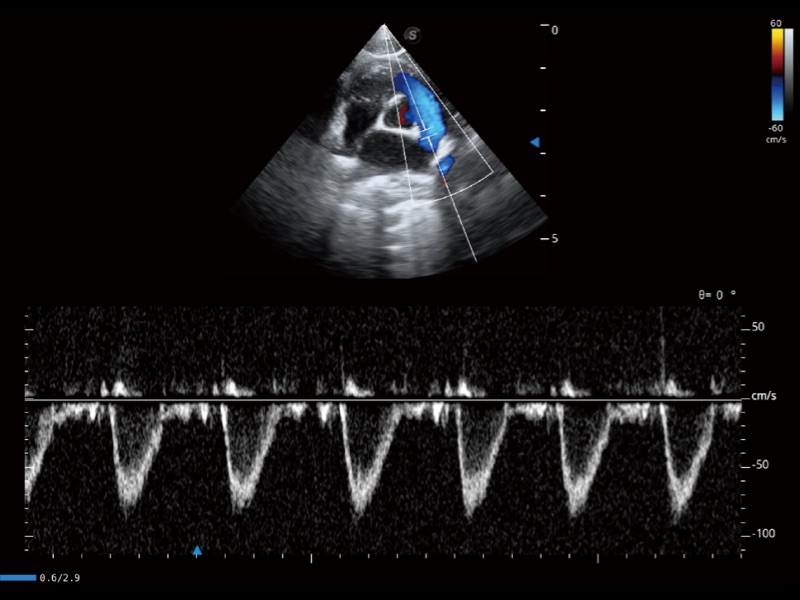

(猫)肺动脉血流频谱

(犬)左室长轴血流

(犬)髂动脉血流